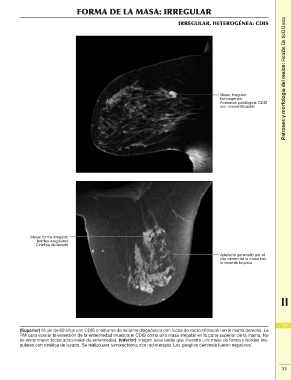

FORMA DE LA MASA: IRREGULAR Patrones y morfología del realce: Realce de tipo masa

IRREGULAR, HETEROGÉNEA: CDIS

Masa: irregular,

heterogénea

Anatomía patológica: CDIS

con microinfiltración

Masa: forma irregular,

bordes irregulares

Cinética de lavado

Artefacto generado por el

clip dentro de la masa tras

la reciente biopsia

(Superior) Mujer de 60 años con CDIS cribiforme de reciente diagnóstico con focos de microinfiltración en la mama derecha. La 121

RM para valorar la extensión de la enfermedad muestra el CDIS como una masa irregular en la parte superior de la mama. No

se encontraron focos adicionales de enfermedad. (Inferior) Imagen axial tardía que muestra una masa de forma y bordes irre- 2

gulares con cinética de lavado. Se realizó una tumorectomía con radioterapia. Los ganglios centinela fueron negativos.